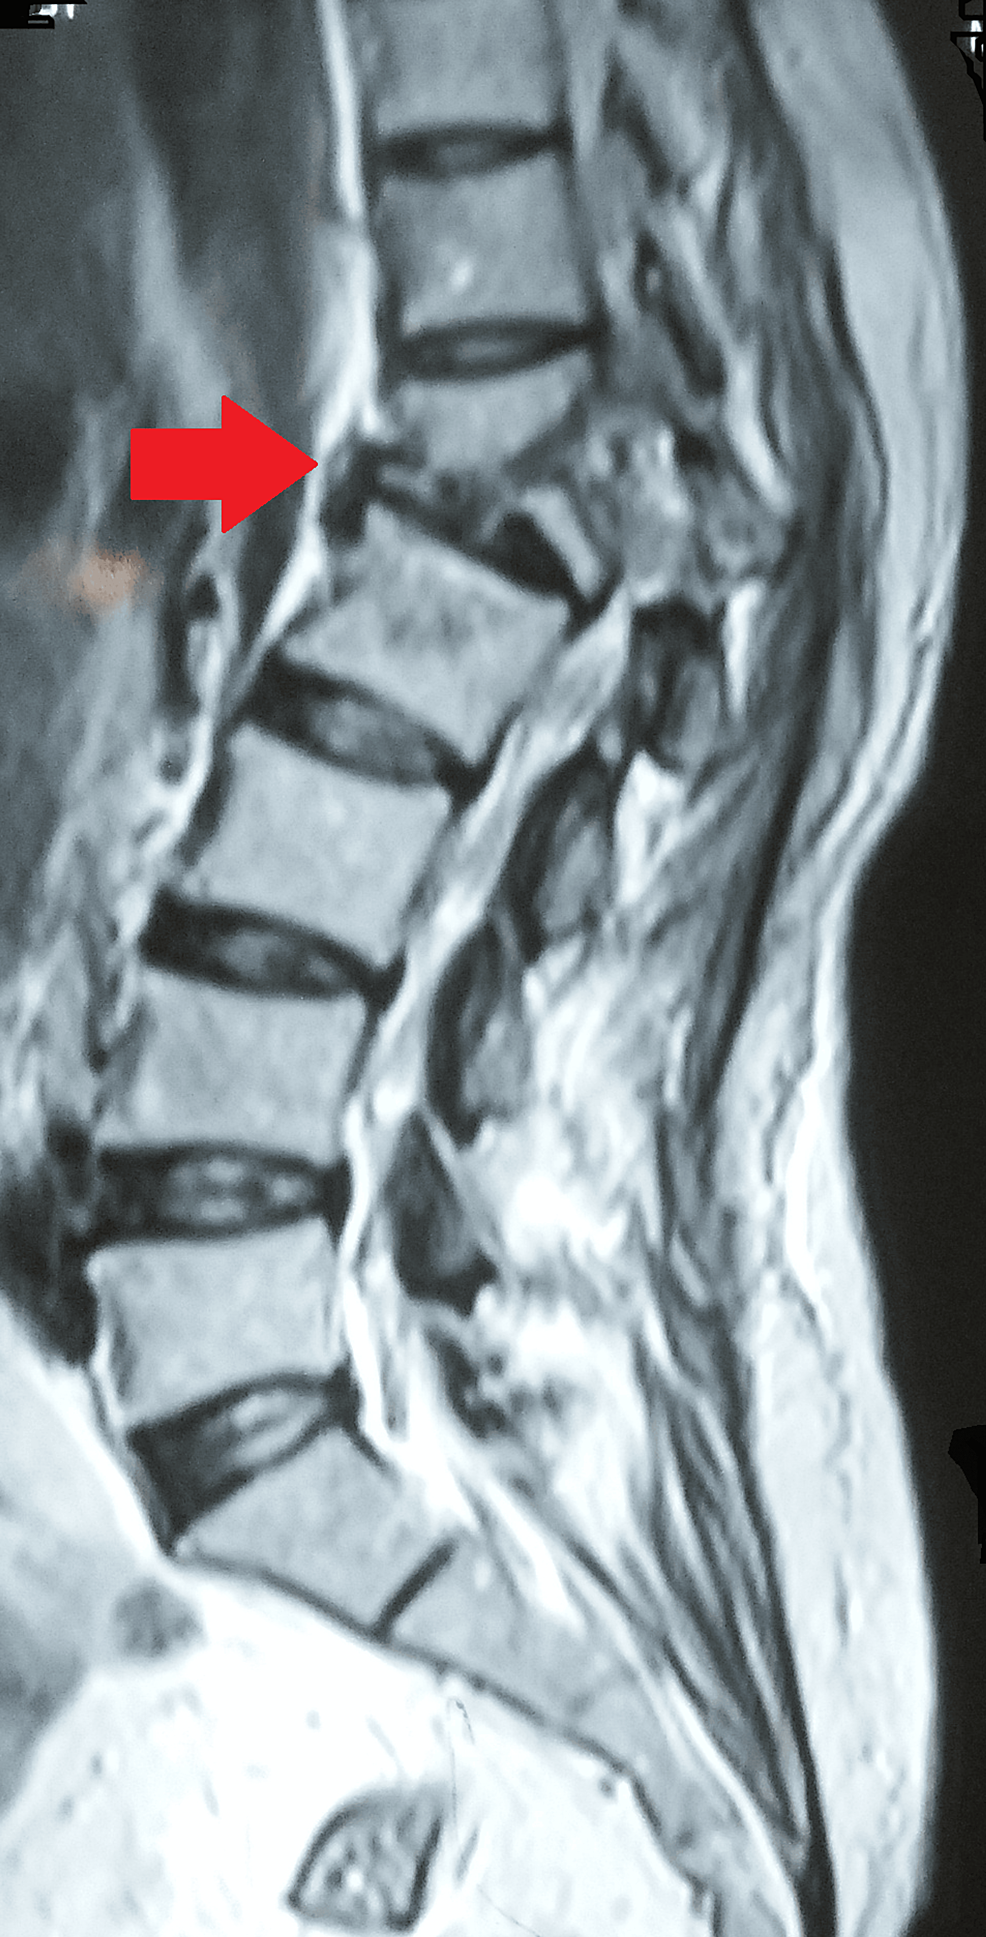

Multidrugresistant tuberculosis of lumbosacral spine producing Multidrug-Resistant Spinal Tuberculosis In both developing and developed countries, tb has been on the rising trend due to factors such as increasing hiv coinfection, multidrug resistance of the organism, and global migration. Spinal tuberculosis (tb) is the most common extrapulmonary form of tuberculosis. It is multiresistant (mdr) if both isoniazid and rifampicin are not effective, and. Multidrug-Resistant Spinal Tuberculosis.

Multidrugresistant tuberculosis of lumbosacral spine producing Multidrug-Resistant Spinal Tuberculosis Spinal tuberculosis (tb) is the most common extrapulmonary form of tuberculosis. It is multiresistant (mdr) if both isoniazid and rifampicin are not effective, and. In both developing and developed countries, tb has been on the rising trend due to factors such as increasing hiv coinfection, multidrug resistance of the organism, and global migration. Multidrug-Resistant Spinal Tuberculosis.

Multidrugresistant tuberculosis of lumbosacral spine producing Multidrug-Resistant Spinal Tuberculosis It is multiresistant (mdr) if both isoniazid and rifampicin are not effective, and. In both developing and developed countries, tb has been on the rising trend due to factors such as increasing hiv coinfection, multidrug resistance of the organism, and global migration. Spinal tuberculosis (tb) is the most common extrapulmonary form of tuberculosis. Multidrug-Resistant Spinal Tuberculosis.

(PDF) Multidrugresistant tuberculosis of lumbosacral spine producing Multidrug-Resistant Spinal Tuberculosis It is multiresistant (mdr) if both isoniazid and rifampicin are not effective, and. Spinal tuberculosis (tb) is the most common extrapulmonary form of tuberculosis. In both developing and developed countries, tb has been on the rising trend due to factors such as increasing hiv coinfection, multidrug resistance of the organism, and global migration. Multidrug-Resistant Spinal Tuberculosis.